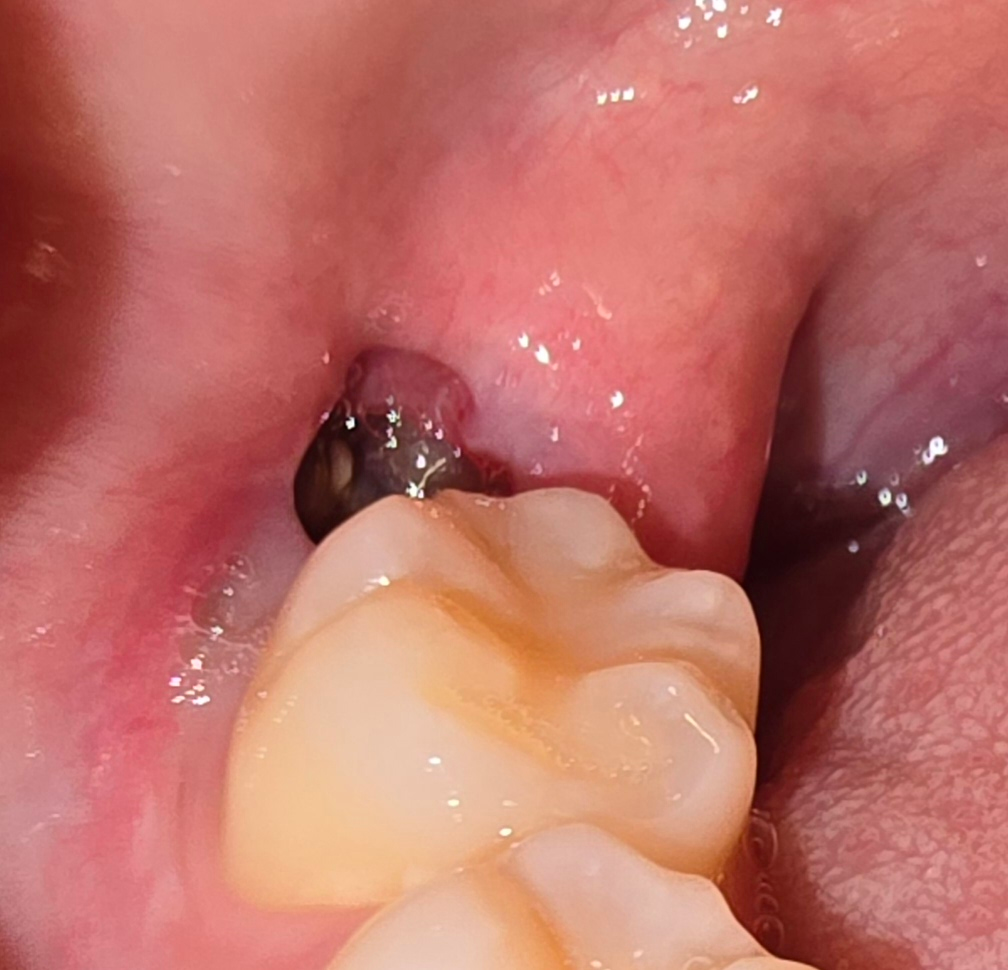

발치한 부위를 자극하게 되면 혈병이 제거되어 치유가 늦어질 수 있습니다. 내부에 이물질이 들어갔다고 해도 내부에 있는 이물질을 억지로 빼내려고 하지 않는 것이 좋습니다. 부드럽게 가글을 해서 제거를 해주는 것이 좋으며 빠지지 않는 것 같은 느낌이 든다면 치과에서 진료를 받아보는 것이 좋습니다. 발질 한 부위는 보통 2주 정도가 지나면 아물기 때문에 그 이전에는 해당 부위를 자극하지 않는 것이 좋습니다

아직 잇몸이 온전히 아물지 않은 상태입니다 초기 치유 후 완전히 잇몸이 아물고 완전히 잇몸뼈가 자라려면 2~3달은 있어야 합니다 그동안 음식물이 껴있지 않도록 칫솔질 및 가글을 부드럽게 잘해주시기 바랍니다